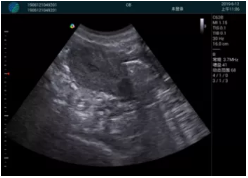

頸動(dòng)脈血流充盈飽滿(mǎn),無(wú)外溢

肝內血管顯示清晰,血流敏感無(wú)外溢